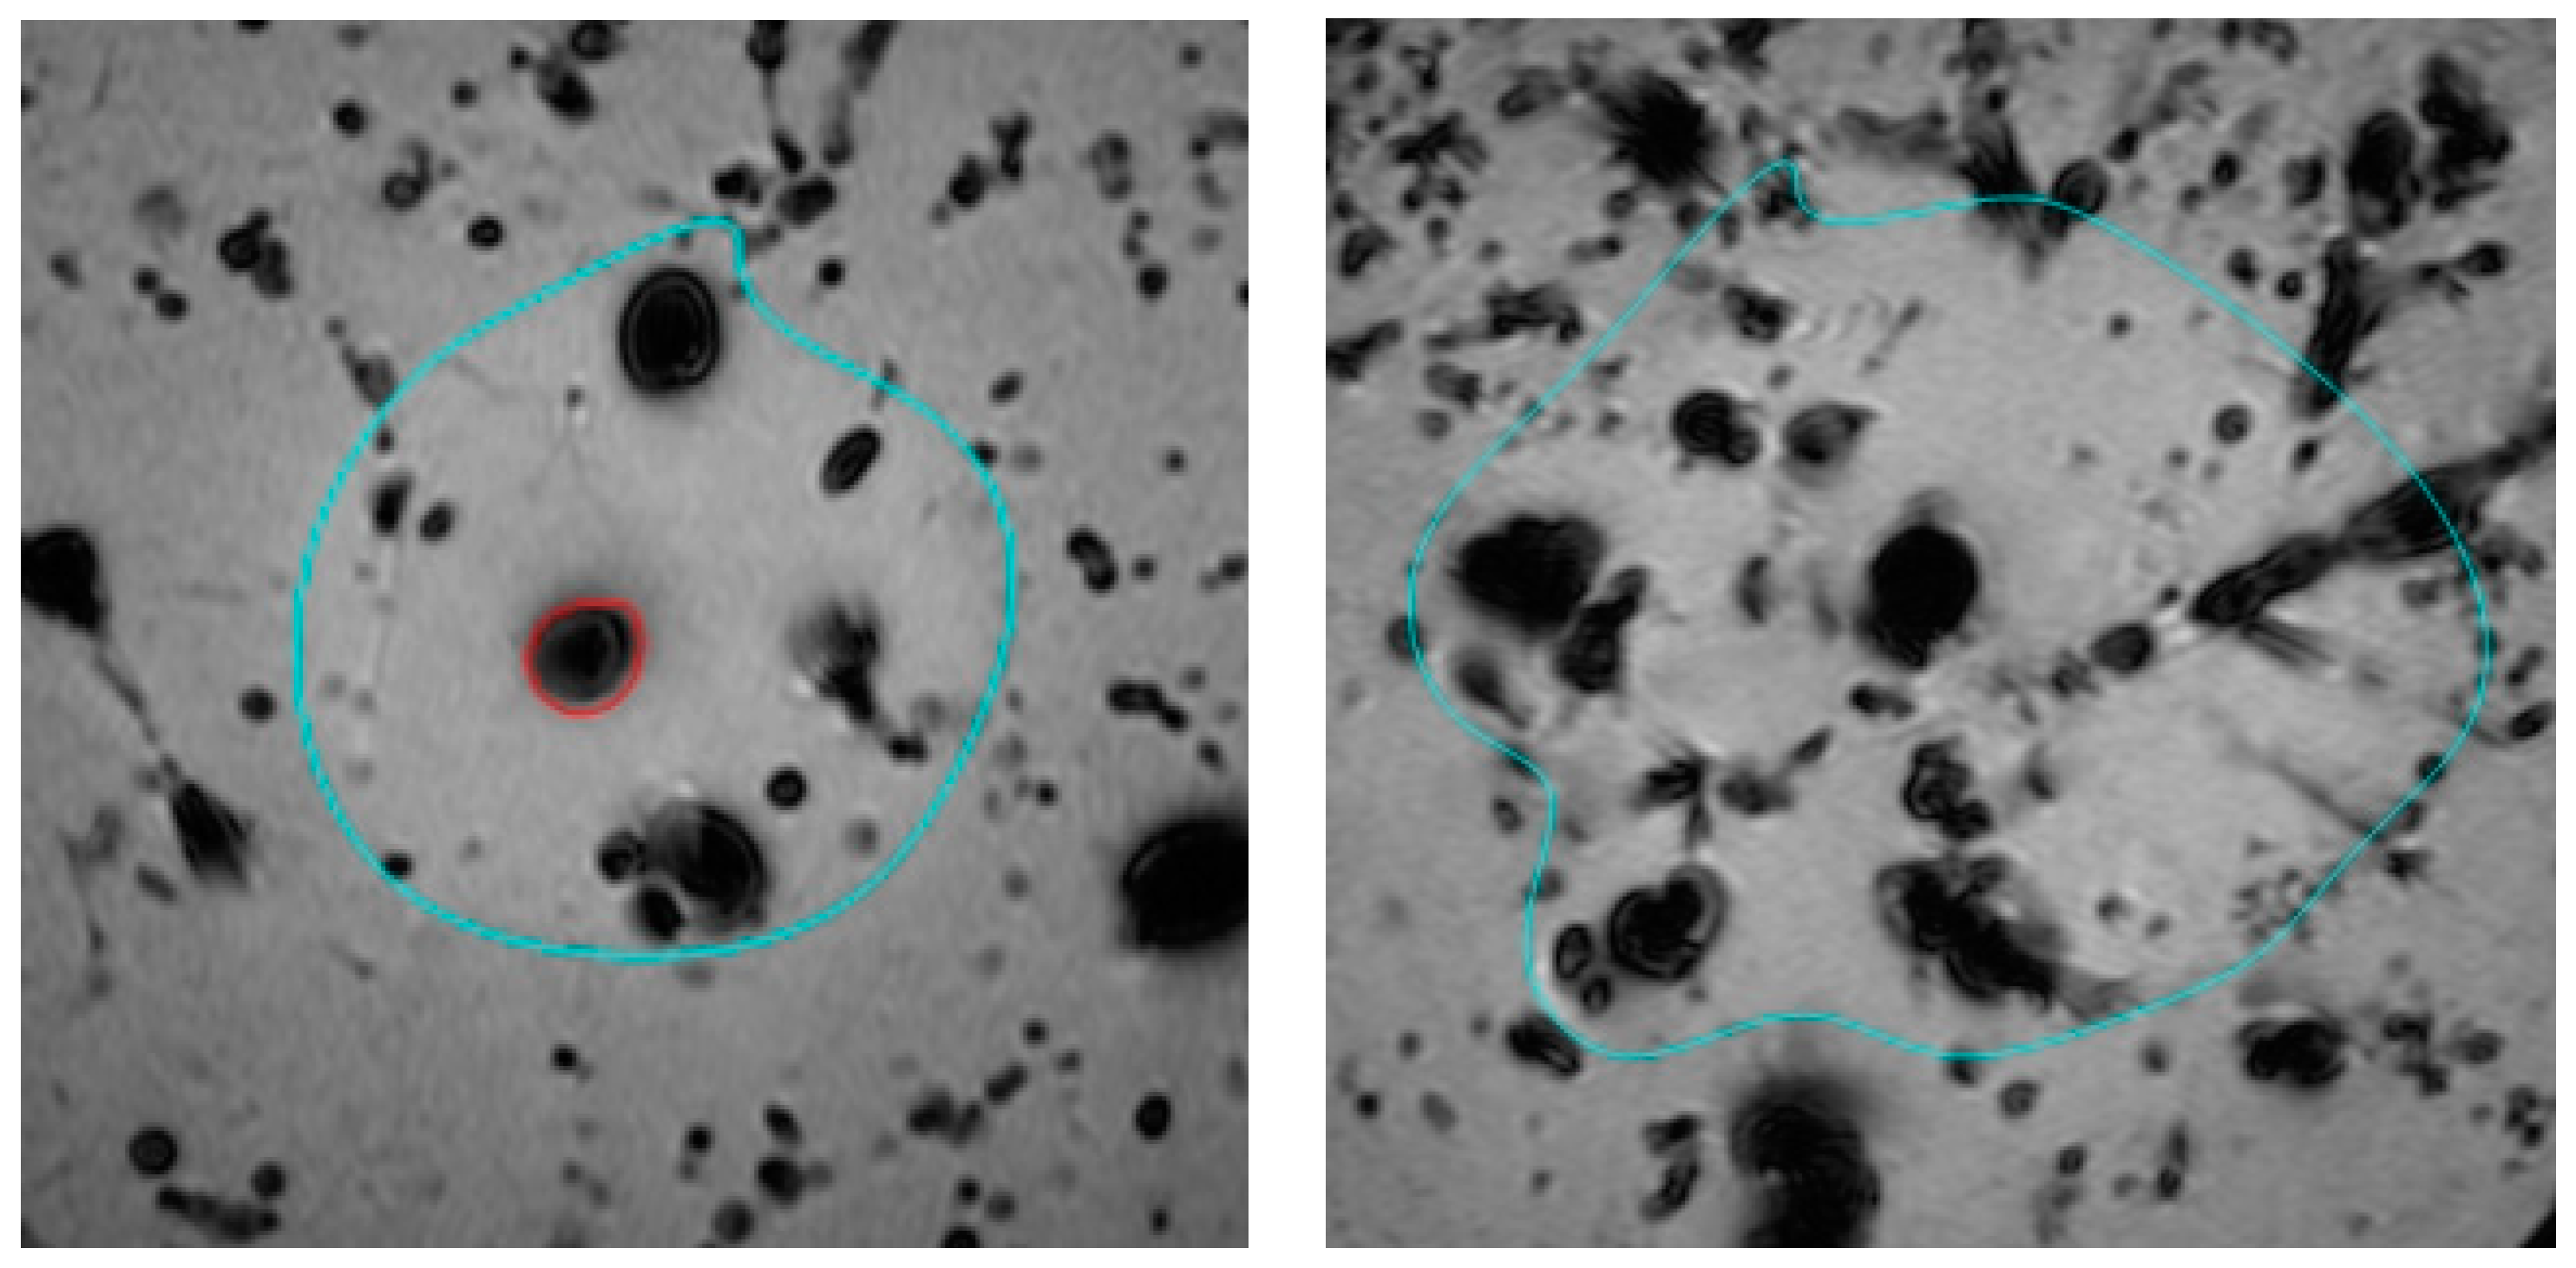

- Mankertz, F.; Gemeinhardt, O.; Felbor, U.; Hadlich, S.; Hosten, N. Spacer-Supported Thermal Ablation to Prevent Carbonisation and Improve Ablation Size: A Proof of Concept Study. Biomedicines 2023, 11, 575. [Google Scholar] [CrossRef]